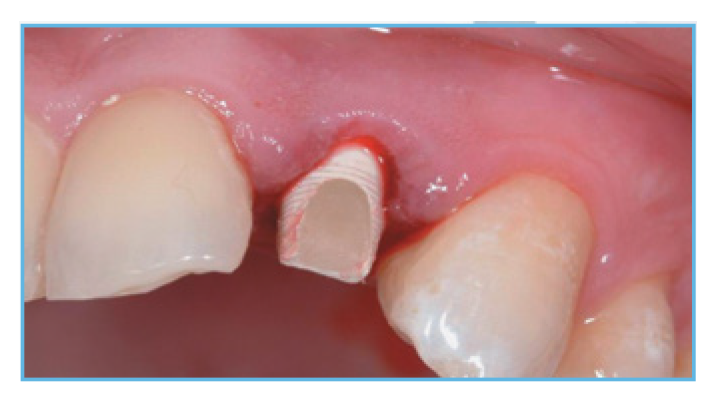

Fig. 3. The PreFormance Post was prepared intraorally to follow the gingival contours.